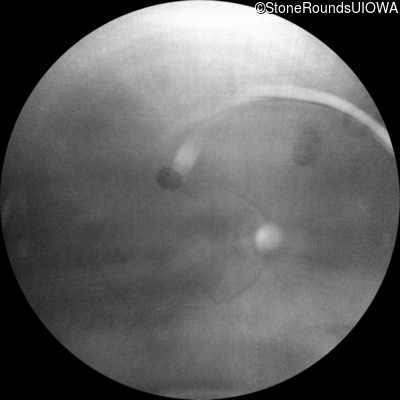

Blue Autofluorescence - Right - 10/300 sc

Exemplar